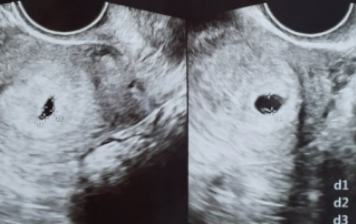

작가의 이전글임신 6주차 초음파, 심장소리 확인하기 시기!